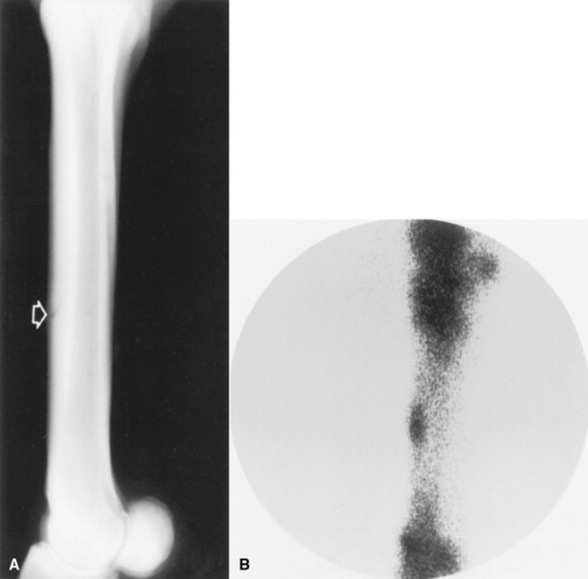

Pain usually was localized to the dorsal aspect of the middiaphysis or near the junction of the proximal and middle thirds of the diaphysis. Initially, pain was mild and elicited from a diffuse area. With continued training, soft tissue thickness became palpable, and diffuse swelling became visible on the dorsum of the metacarpus. Later, soft tissue thickness and swelling became more focal unless hard work was continued. Approximately 2 to 3 weeks after pain first was detectable, discrete hard swellings could be palpated on the dorsum of the metacarpus. Radiographic abnormalities often are absent in horses with acute bucked shins.412 The dorsal cortex thickens during adaptation to the stresses associated with training,413 but indistinct periosteal proliferation, subperiosteal demineralization,412 or subperiosteal radiolucencies support a diagnosis of bucked shins. Even in the absence of radiographic abnormalities, bone scintigraphy demonstrates a diffuse region of intense radiopharmaceutical uptake in the dorsal cortex of affected horses414 (Fig. 38-43).

image

Fig. 38-43 A, Lateromedial radiograph, and B, lateral scintigram, of the third metacarpal bone of a horse with bucked shins. Although dorsal cortical thickening is present, distinct radiographic changes associated with acute metacarpal disease cannot be detected. However, diffuse exaggerated radiopharmaceutical uptake is demonstrated in the dorsal cortex.

Courtesy P.D. Koblik.